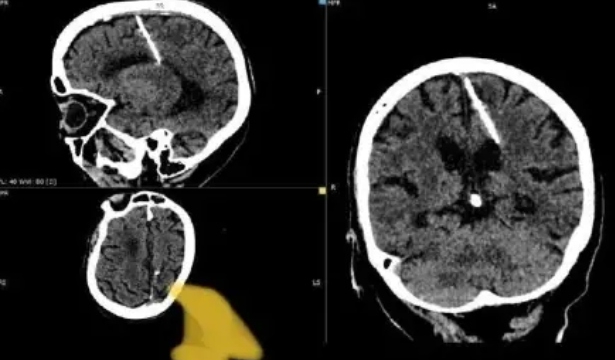

A senhora de 80 anos, nasceu no final da década de 1930 e tomou conhecimento de sua condição por meio de um exame de tomografia | Foto: Reprodução: Internet

Uma notícia está causando grande comoção na Rússia, após a descoberta de uma agulha de três centímetros no cérebro de uma idosa russa, com 80 anos de idade. A notícia rapidamente se tornou viral, com as especulações acercando a origem do objeto, proporcionando uma viagem intrigante pela história russa.

A senhora de 80 anos, nasceu no final da década de 1930 e tomou conhecimento de sua condição por meio de um exame de tomografia. A época de nascimento da idosa foi marcada pela extrema escassez de alimentos, ocasionada pela Segunda Guerra Mundial, o que, segundo especulações, teria levado seus pais a realizar uma tentativa de infanticídio logo após o seu nascimento.

De acordo com os médicos responsáveis pelo diagnóstico da idosa, a agulha teria sido inserida em seu cérebro através de sua moleira, um espaço macio e flexível presente no topo do crânio dos bebês. Este espaço é preenchido por ossos sólidos à medida que a criança cresce, o que pode explicar a falta de qualquer cicatriz óbvia. Por essa razão, suspeita-se que a agulha tenha sido colocada quando ela ainda era um bebê.